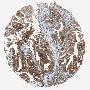

ENDOMETRIAL CANCER - Protein expressioni

A mouse-over function shows sample information and annotation data. Click on an image to view it in a full screen mode. Samples can be filtered based on level of antibody staining by selecting one or several of the following categories: high, medium, low and not detected. The assay and annotation is described here.

Note that samples used for immunohistochemistry by the Human Protein Atlas do not correspond to samples in the TCGA dataset.

Antibody stainingi

Antibody staining in the annotated cell types in the current human tissue is reported as not detected, low, medium, or high, based on conventional immunohistochemistry profiling in selected tissues. This score is based on the combination of the staining intensity and fraction of stained cells.

Each image is clickable and will lead to virtual microscopy that enables deeper exploration of all samples and also displays staining intensity scores, fraction scores and subcellular localization as well as patient and tissue information for each sample.

Antibody HPA005741

Antibody HPA011731

Antibody CAB008366

Staining

High

Adenocarcinoma, NOS